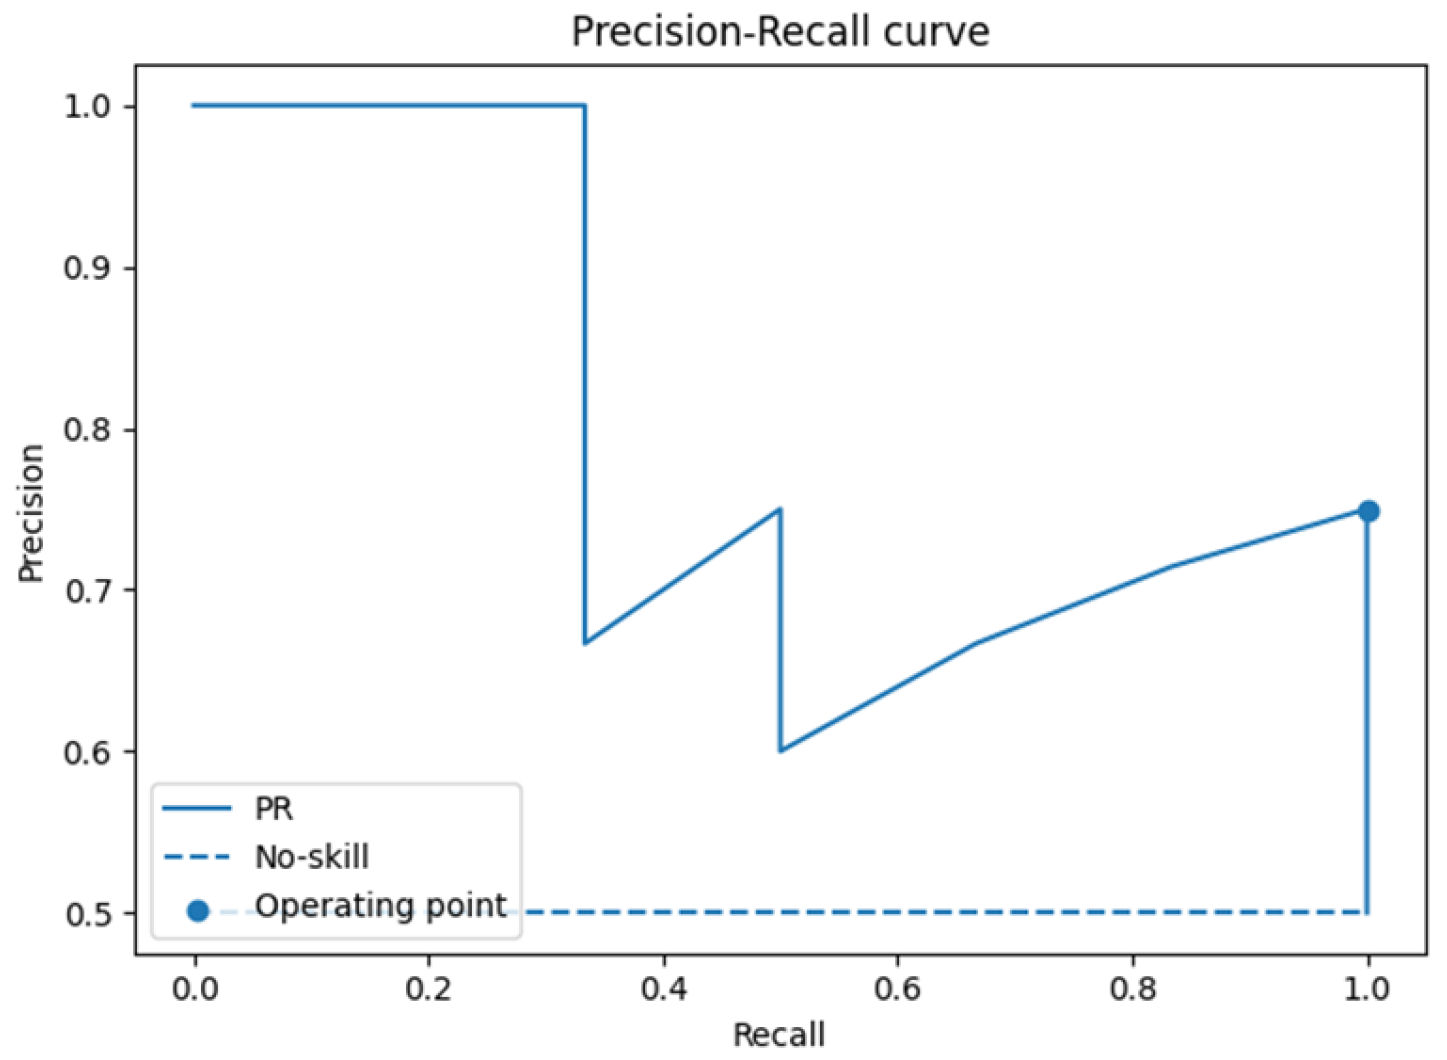

3.1. Leave-One-Patient-Out Cross-Validation (LOPO-CV)

3.2. Radiomic Feature Interpretability and Clinical Relevance

4.2. SVM Classification and Model Robustness